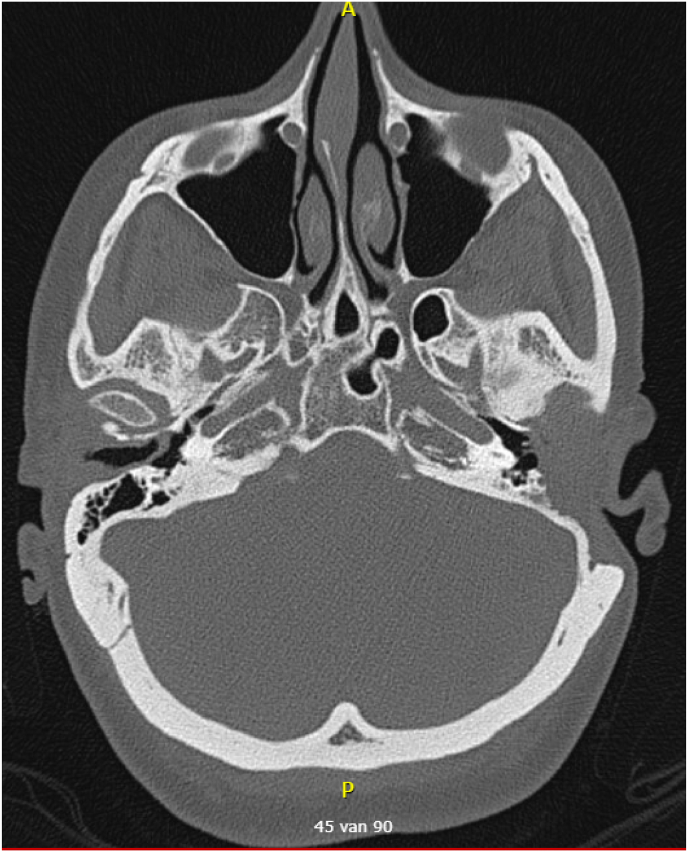

Abstract Image